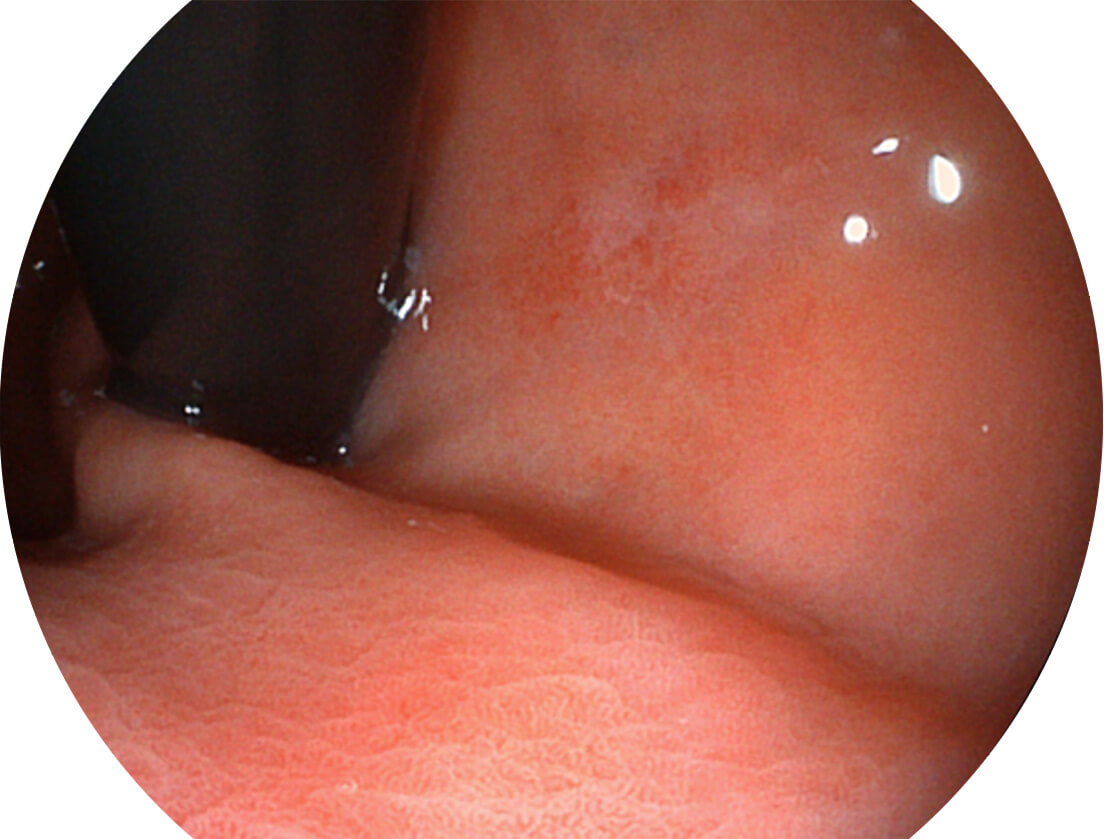

聚谱成像技术

Spectral Focused lmaging, SFI

图像具有高亮度、高黏膜血管颜色对比度的特点,且不改变粘液、食物残渣、粪便的基本颜色,可在中远景下进行观察,助力消化道早期疾病的诊断。

• 白光图像 SFI图像